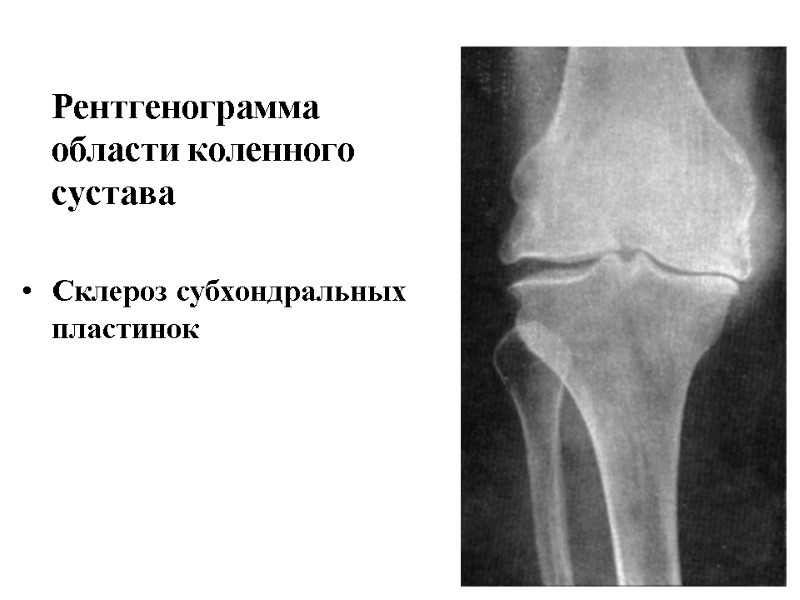

Рентгенограмма области коленного сустава Склероз субхондральных пластинок